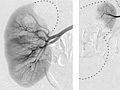

An angiogram is an X-ray test that uses a special dye and camera (fluoroscopy) to take pictures of the blood flow in an artery (such as the aorta) or a vein (such as the vena cava). An angiogram can be used to look at the arteries or veins in the head, arms, legs, chest, back, or belly.

During an angiogram, a thin tube called a catheter is placed into a blood vessel in the groin (femoral artery or vein) or just above the elbow (brachial artery or vein). The catheter is guided to the area to be studied. Then an iodine dye (contrast material) is injected into the vessel to make the area show clearly on the X-ray pictures. This method is known as conventional or catheter angiogram. The angiogram pictures can be made into regular X-ray films or stored as digital pictures in a computer.

When the catheter is in place, the dye is injected through it. You may be asked to take a breath and hold it for several seconds. Several X-ray pictures will be taken one after another. These will be available right away for your doctor to look at. You need to lie very still so the pictures are clear. More pictures may be taken.

An angiogram is an X-ray test that uses a special dye and camera (fluoroscopy) to take pictures of the blood flow in an artery (such as the aorta) or a vein (such as the vena cava). Your doctor may tell you some results right after the test. Full results are usually ready the same day.